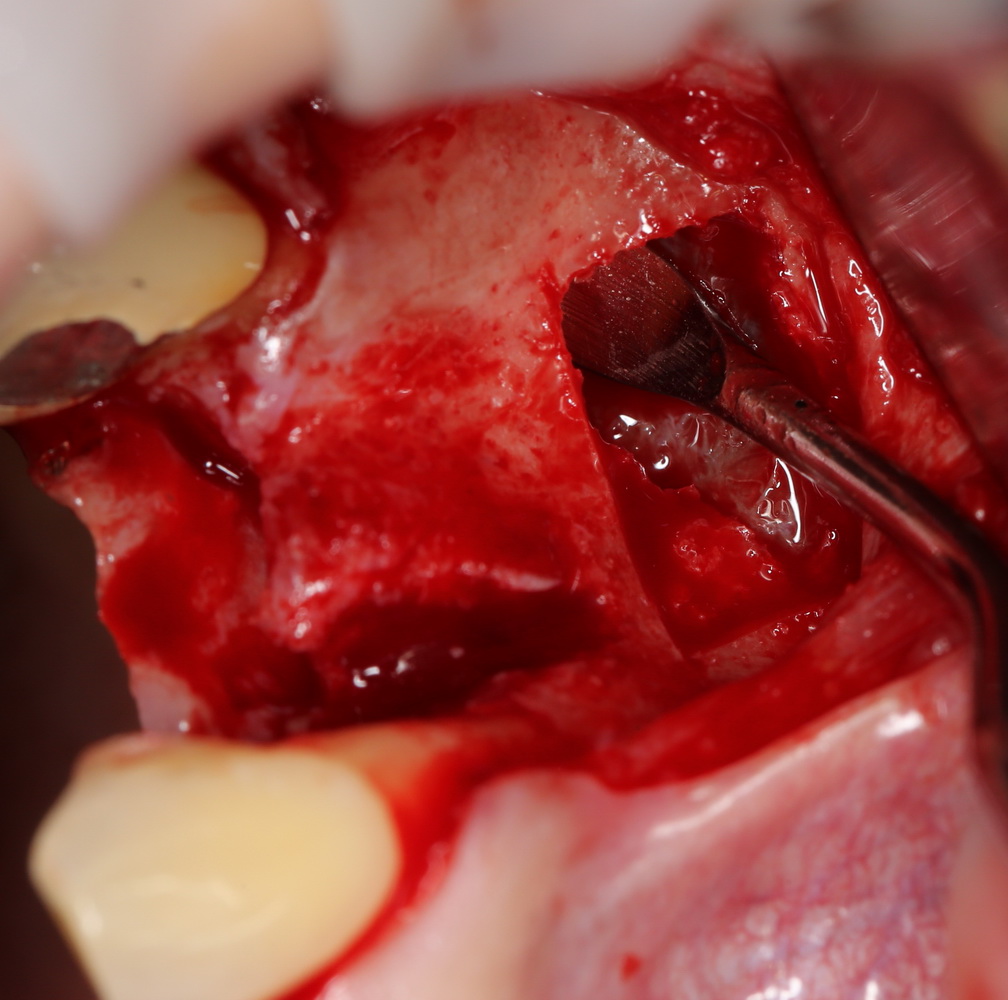

И вроде бы, все неплохо, но когда мы скелетируем костную ткань, то видим следующее:

Можно ли поставить импланты? Теоретически, если использовать импланты диаметром 3,0 мм — вполне возможно. Но как это будет потом выглядеть? Большие коронки на тоненьких имплантах с тонкой десной? А если эти зубы еще попадают в эстетически значимую зону и видны при улыбке? А если это еще и девушка, которая собирается замуж? И вот тут встает вопрос о размерах и позиционировании имплантов, который тянет за собой вопрос об остеопластике.